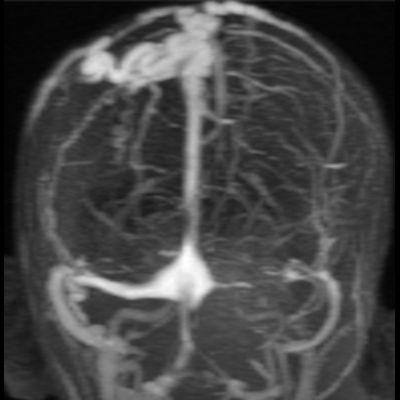

10 yaş, E

Vertekste ele gelen şişlik

Sinüs Pericranii

SİNÜS PERİKRANİİ